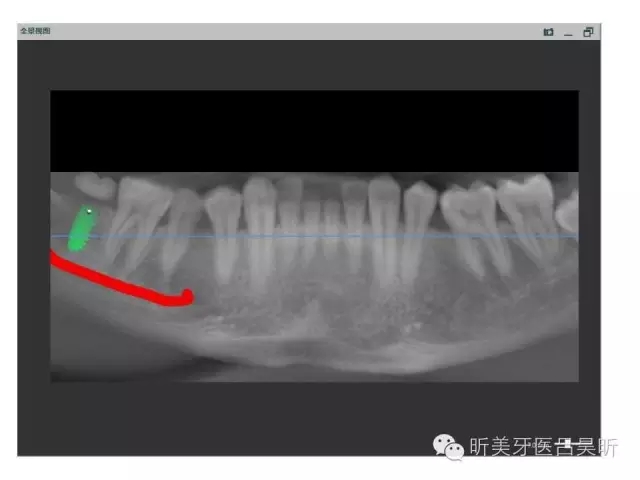

術(shù)前口內(nèi)掃描,設(shè)計冠修復(fù)方式和種植位點

可見種植位點舌側(cè)區(qū)凹陷,牙槽骨上部舌傾明顯。

擬定種植三維方向

以修復(fù)為導(dǎo)向的種植位點設(shè)計